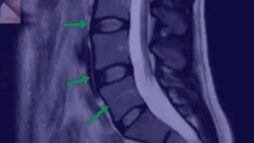

- Что оценивать на МРТ

- Как выглядит идеальный позвоночник

- Как выглядит плохой позвоночник

- Как выглядит позвоночник спортсмена

- Надрыв кольца на МРТ, поясничный прострел

- Протрузия на МРТ

- Грыжа осложненная стенозом канала

- Секвестрированная грыжа

- Артроз на МРТ

- Позвоночник пациента, занимающегося тяжелым физическим трудом

- Остеопороз, перелом позвонка

- Кисты на суставах

- Гипертрофия фасетки

- Листезы

- Гемангиомы

- Гипертрофия желтой связки

- Грыжа Шморля